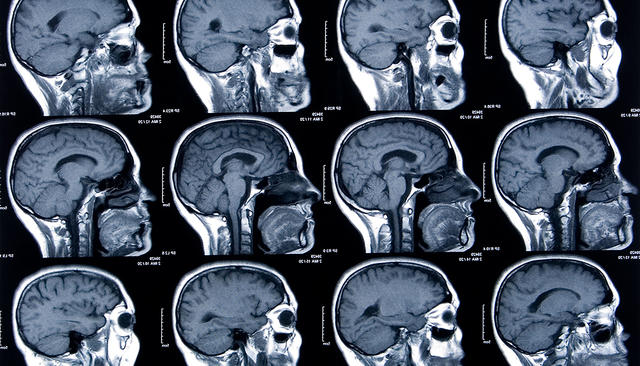

Невролог Фил Кеннеди прославился в 1998 году, когда он вместе с нейрохирургом Роем Бэкэем вживил в мозг пациента электроды для передачи сигнала компьютеру. Парализованный пациент научился водить курсором по экрану и набирать сообщения (функция щелчка активировалась, если он дергал плечом). До этого он мог общаться только моргая. Кеннеди и Бэкэй стали звездами, а Джонни Рэй — так звали пациента — первым человеком-киборгом. В 2014-м Фил Кеннеди решил вживить импланты в свой собственный мозг. Его историю рассказывает журнал Wired.

Американский невролог Фил Кеннеди изобрел новый подход. В мозг вживлялись конусообразные стеклянные полые импланты, через которые проходил золотой провод. В конус Кеннеди добавлял маленький кусочек седалищного нерва; благодаря ему конусы приживались в тканях, при этом закрепившись на одном месте. Впрочем, для вживления конусов в мозг человека вместо седалищного нерва Кеннеди использовал искусственный раствор для ускорения роста клеток.